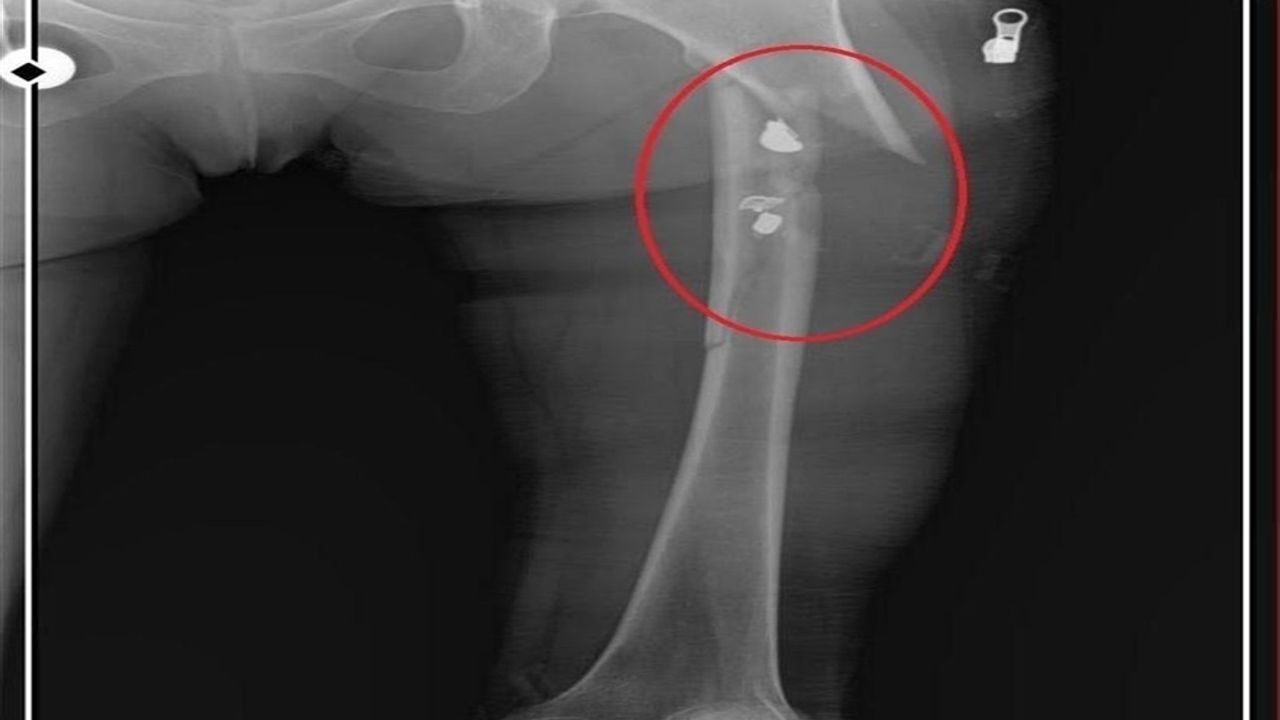

Osmangazi ilçesi Küplüpınar Mahallesi'nde 2023 Haziran ayında meydana gelen olayda; İlyas Sarıkaya, mahalleden arkadaşı Recep Özaslan'ı, Alzheimer hastası annesi A.S. ve sevgilisi Fatma O. ile birlikte yaşadığı eve çağırdı. İddiaya göre; uyuşturucu etkisinde olan Sarıkaya, sevgilisiyle ilişkisi olduğunu düşündüğü Özaslan'ı tabancayla vurdu ardından da 'acı çekmesin' diye 2 kez daha ateş etti. Özaslan, beline ve göğsüne isabet eden kurşunlarla hayatını kaybetti.

İlyas Sarıkaya, sevgilisi Fatma O.'yu da 8 kurşunla vurup, yaraladı. Arkadaşı Özaslan'ın cesedini önce çarşafa sonra da streç filme sarıp bantlayan Sarıkaya, eczaneden aldığı sargı bezi ve ilaçlarla pansumanını yaptığı sevgilisine yaralı haldeyken 21 gün boyunca cinsel saldırıda bulundu.